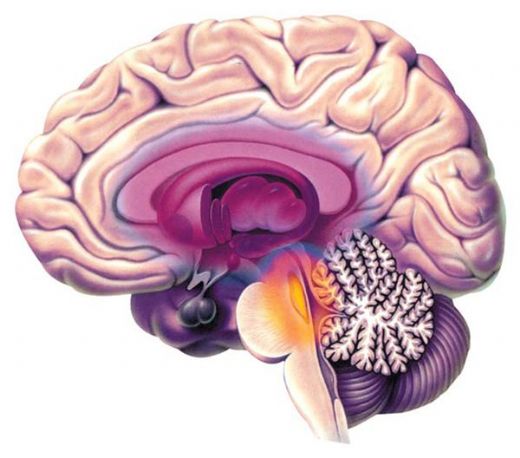

Beyin Dokusu Türleri ve Özellikleri Beyin, merkezi sinir sisteminin en önemli organı olup, karmaşık yapısıyla birçok işlevi yerine getirmektedir. Beyin dokusu, genel olarak iki ana türden oluşmaktadır: gri madde ve beyaz madde. Bu makalede, beyin dokusu türleri ve özellikleri detaylı bir şekilde incelenecektir. Gri Madde Gri madde, beyin yüzeyinde yer alan ve nöron hücre gövdelerinin (soma) yoğun olarak bulunduğu bölgedir. Gri maddenin başlıca özellikleri şunlardır:

Beyaz Madde Beyaz madde, beyin içerisindeki nöronların aksonlarının yoğun olarak bulunduğu bölgedir. Aksonlar, nöronlar arasındaki iletişimi sağlamak için elektriksel sinyaller ileten uzun uzantılardır. Beyaz maddenin özellikleri şunlardır:

Beyin Dokusu Hücreleri Beyin dokusu, nöronlar ve glia hücreleri olmak üzere iki ana hücre türünden oluşmaktadır. Nöronlar, sinyalleri ileten ve bilgiyi işleyen temel hücrelerdir; glia hücreleri ise destekleyici işlevler üstlenir. Glia hücrelerinin türleri ve işlevleri şunlardır: